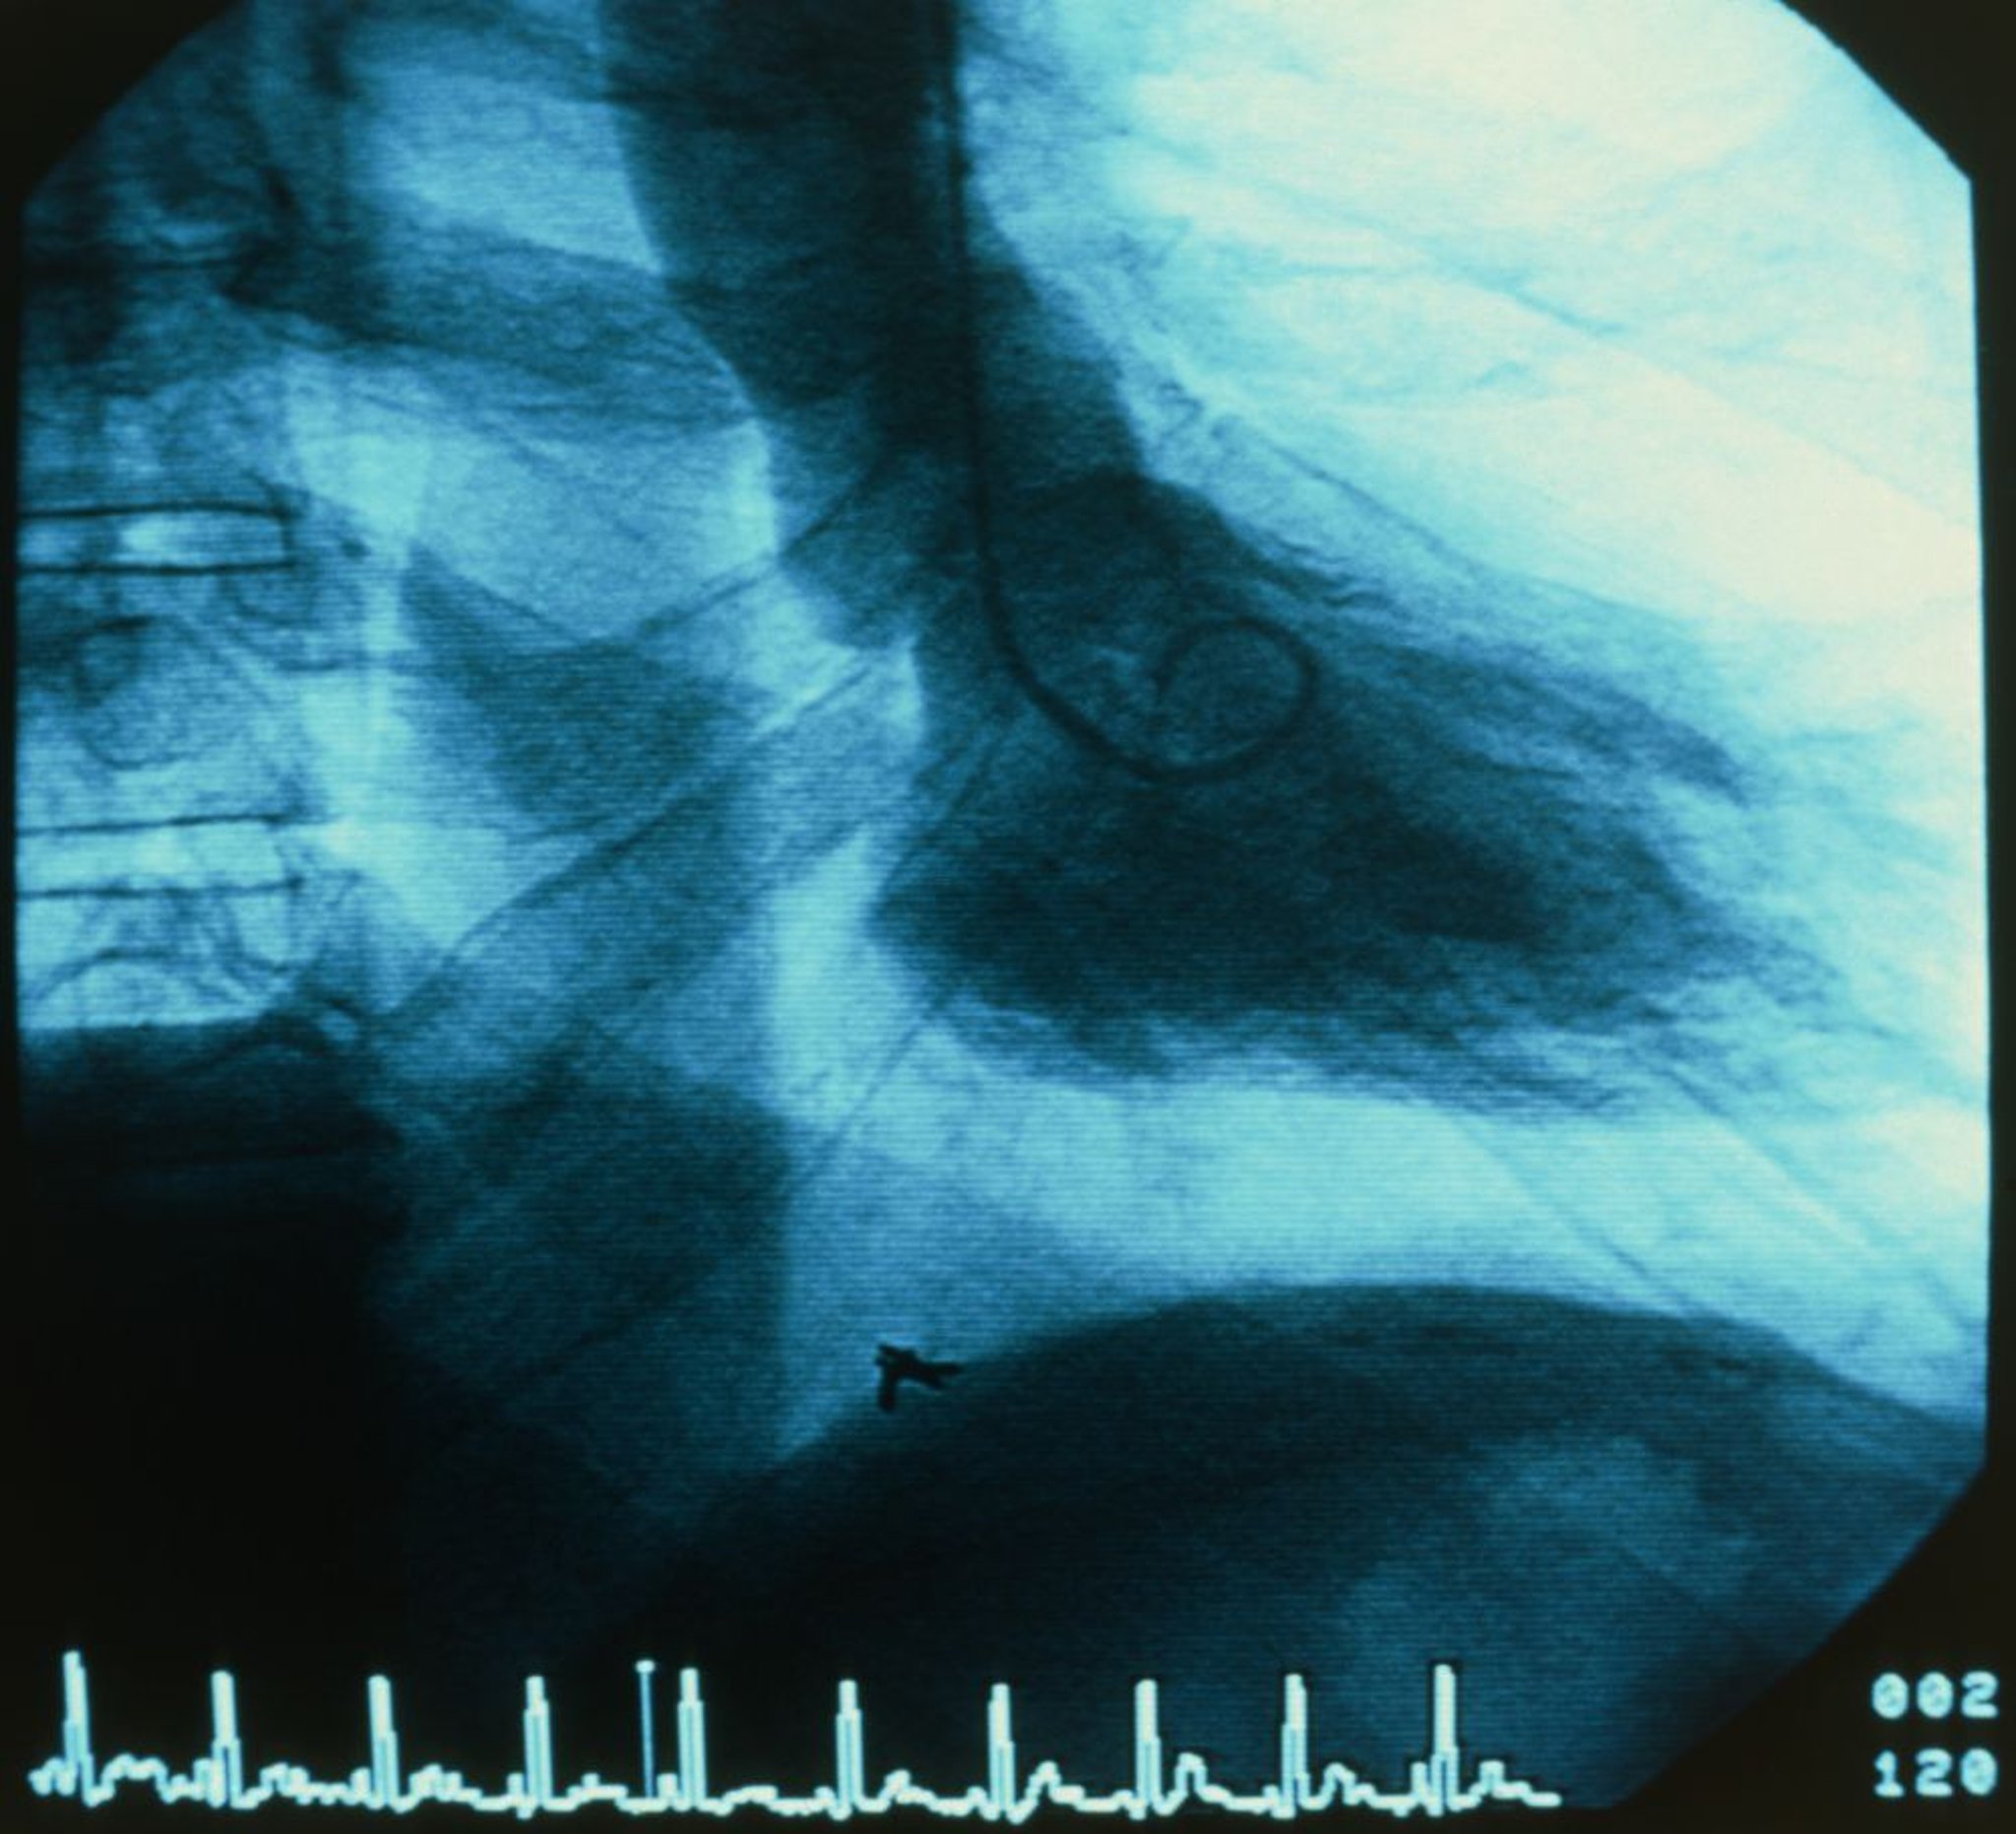

Ventriculography (LV Gram)

A catheter (center) is inserted into the left ventricle (LV). Contrast is then injected into the LV under fluoroscopy and the ejection fraction is visually estimated.